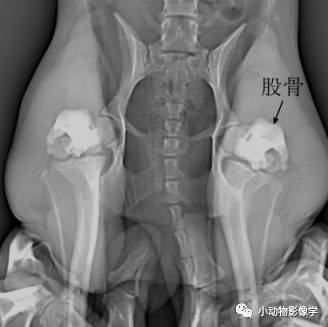

(5)骨盆

①侧位:毛巾卷置于两侧跗部,使两股骨平行,X光束集中于髋关节

②髋关节屈曲VD照:

A.动物仰卧,后肢屈曲外展

B.用于评估股骨头股骨颈、髋臼深度和髋关节契合度

③髋关节伸展VD照

A.动物仰卧,后肢伸展并与骨盆平行

B.需要稍稍向内用力,人的手抓住两侧跗部。大型犬可以用胶带或绳子将膝关节处捆住。

④半轴X光影像:双侧股骨平行且部分伸展,两股骨之间放置毛巾卷并用力下压,双侧跗部向中间加压,由于支撑物的作用关节可能会分离。

侧位

毛巾卷的位置

骨盆伸展VD位

骨盆屈曲VD位

骨盆半轴照,E伸展,N正常

骨盆半轴照